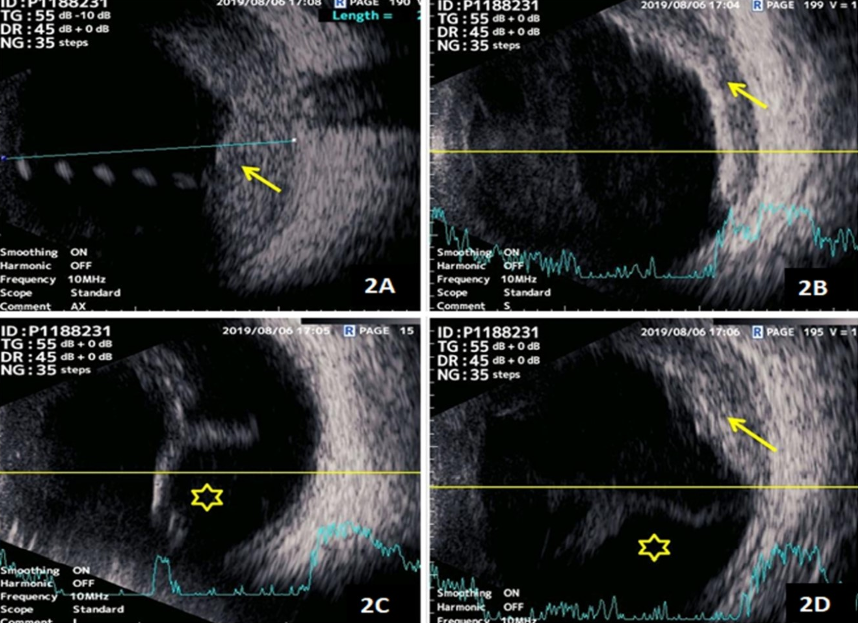

Right-eye ultrasound B-scan in the axial scan showed an elevated mass lesion in the choroid with moderate to high internal echogenicity. The transverse and dynamic ultrasound B-scans also showed the presence of an exudative retinal detachment in the inferior scans with elevated choroidal lesions in the superior scans (Figure 2 [Fig. 2]).

Figure 2: A) Right-eye ultrasound B-scan in the axial scan showed an elevated mass lesion in the choroid with moderate to high internal echogenicity (yellow arrow). B–D) The transverse and dynamic ultrasound B-scans also showed presence of exudative retinal detachment in the inferior and nasal scans (yellow asterisk in 2C and 2D) with elevated moderate to high echogenic choroidal lesions in the superior and nasal scans (yellow arrow in 2B and 2D).